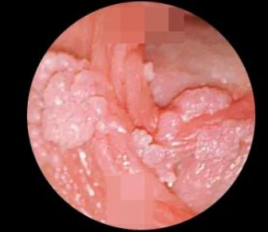

二、主要症状:尖锐湿疣(长什么样)

形态:菜花状、乳头状、鸡冠状、颗粒状

颜色:粉红、肤色、灰白

质地:柔软,触碰易出血

应大哥们要求,上点图片给大家

大家可以看看这些分别 是哪个部位的